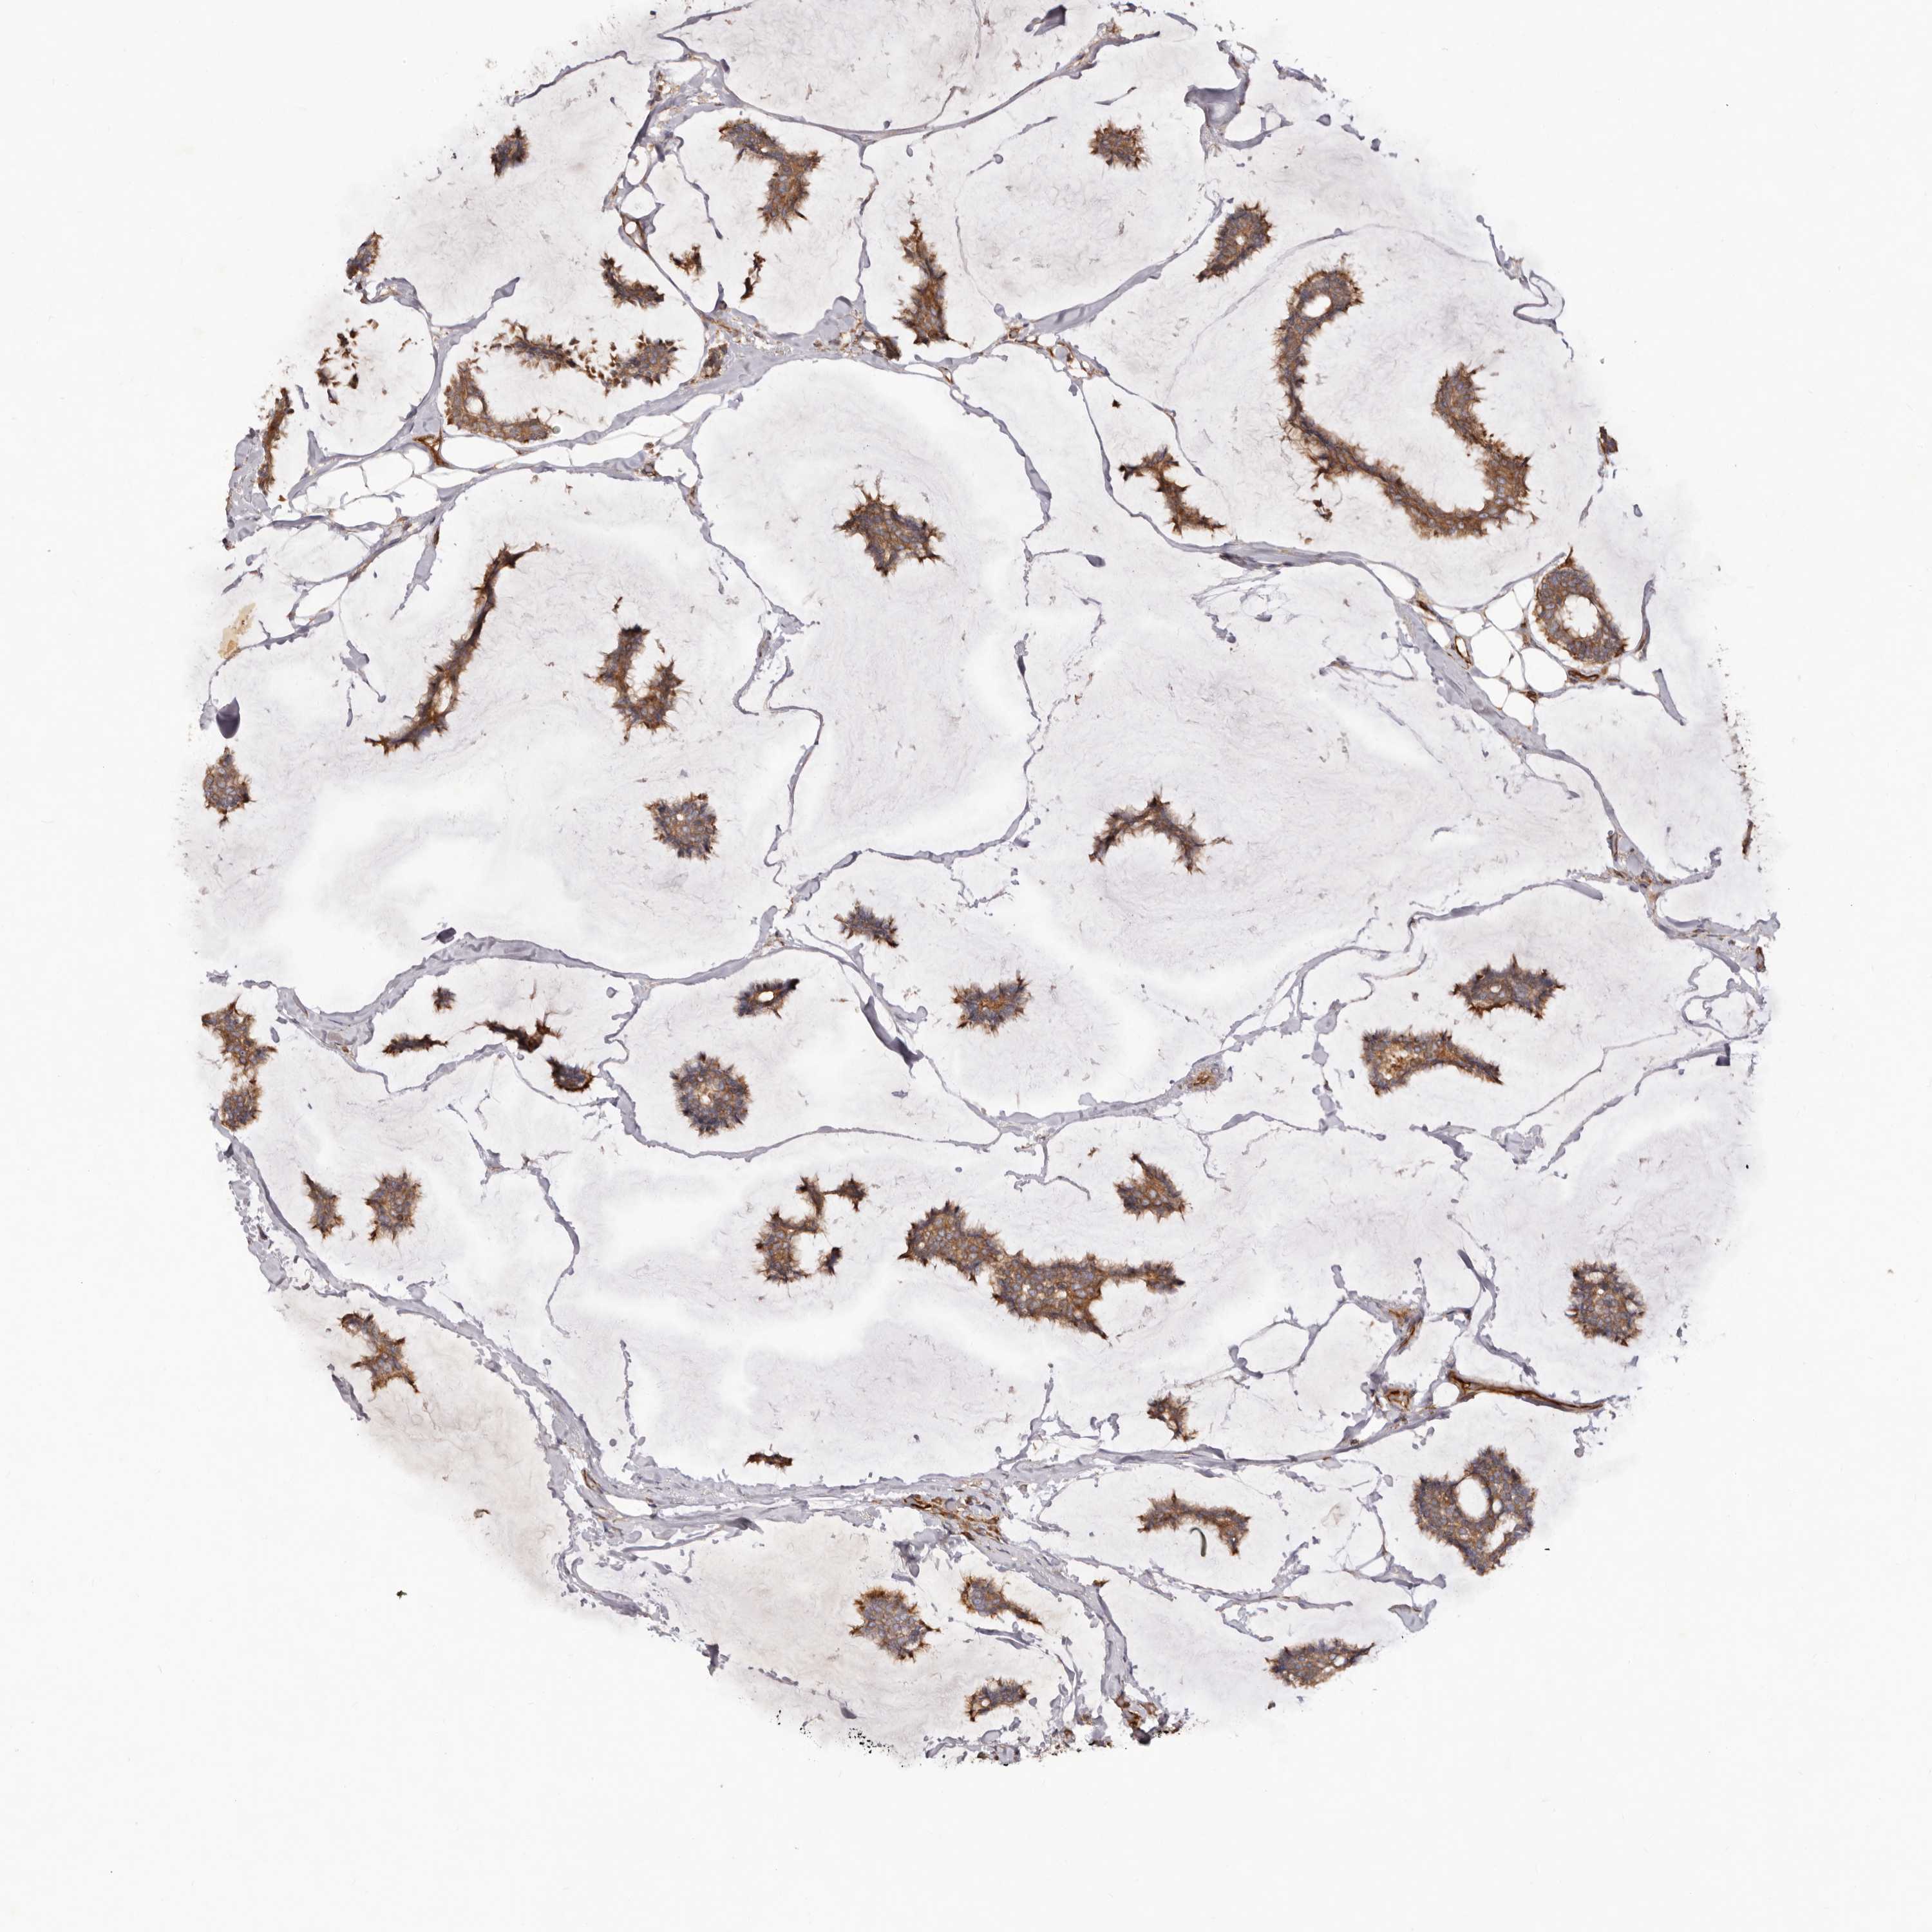

CANCER BREAST CANCER Show tissue menu

BRCA TCGA BRCA VALIDATION PROTEIN EXPRESSION